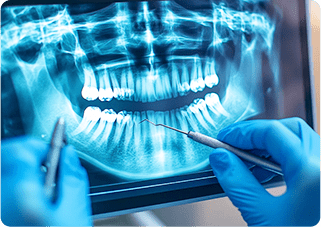

歯科用CTや電気歯髄診断器を用いて、根管の状態を精確に診断し、治療計画を立てます。

歯科用CT

立体的に撮影できる歯科用CTは、根の形や曲がり具合、感染の広がりなどを正しく把握するために欠かせません。より的確な診断と治療計画が可能になります。